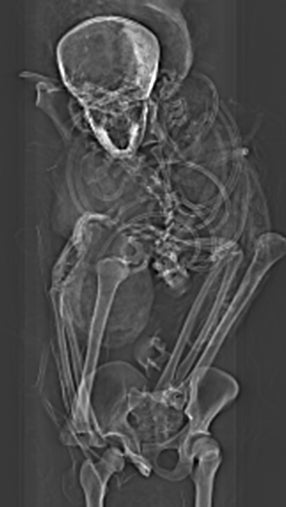

In an effort to answer these questions, a team of archaeologists led by Sahar Saleem, a professor of radiology at Cairo University, used computerized tomography (CT) to re-analyze the mummy, which is kept at the Cairo Egyptian Museum. The research team, which included Zahi Hawass, an archaeologist with Egyptian Ministry of Antiquities, also reviewed the archaeological literature and evaluated five Asian weapons previously uncovered at Tell-el-Dabaa. These weapons—three daggers, a battle-axe, and a spearhead—date back to the Asian Middle Bronze Age Culture II, which coincides with the reign and death of Seqenenre.

The new analysis showed that the mummy is in very bad shape. The head is no longer connected to the body, many vertebrae and ribs are loose, and there’s very little soft tissue or muscles left on the bones.

The investigation showed that Seqenenre was around 40 years old when he died and that he stood 5’6” (167 cm) tall.

A desiccated, shrunken brain was found on the left side of the skull, and it doesn’t appear that any attempt was made by his embalmers to remove it, unlike his other organs. In fact, no evidence of embalming materials could be found.

Seqenenre had no bodily fractures, but his head and face were severely injured. The large fracture on his forehead was attributed to a “heavy sharp object like a sword or an axe,” according to the paper. The location of this injury suggests an assailant delivered the killing blow from a position above the pharaoh. A double-edged weapon, like a bronze battle-axe, likely caused the “gaping fracture” above Seqenenre’s right eyebrow, and some kind of blunt force object, like an axe handle, was responsible for multiple blows on the pharaoh’s face, according to the paper. A penetrating wound below the mummy’s left ear and into the base of his skull was likely caused by a spearhead.

The researchers said any one of these injuries would’ve been fatal; such “severe craniofacial trauma could have caused fatal shock, blood loss, and/or intracranial trauma,” they wrote. The CT scans confirmed that all injuries to the skull and face were inflicted at the time of death, as there was no evidence of healing.

The condition of the pharaoh’s hands and wrists points to a condition known as “cadaveric spasm,” which “typically affects the hands and limbs of individuals who were subjected to violent deaths and whose nervous systems were disturbed at the moment of death,” wrote the authors. In this case, the peculiar and unorthodox hand positioning suggests the pharaoh’s wrists were tied together, likely behind his body, when he was killed. This could also explain why Seqenenre had no defensive wounds on his hands or arms.